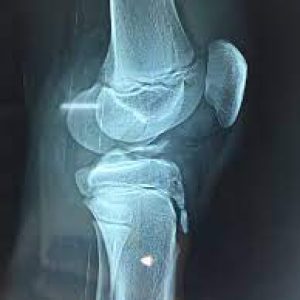

1. Preoperative Assessment: Comprehensive evaluation, including physical examination, imaging studies (X-rays, MRI), and assessment of knee stability and function.